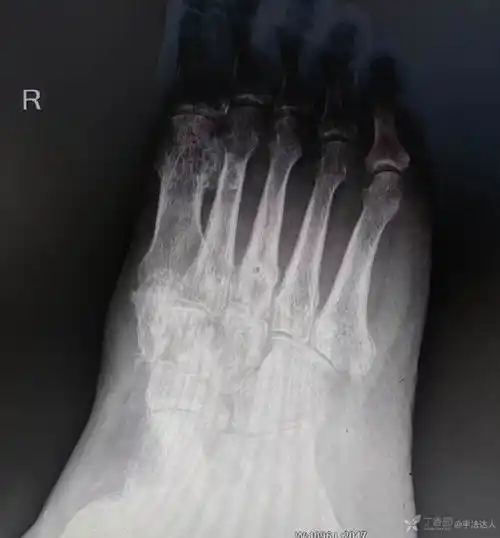

男48岁第一第二楔骨骨折术后半年有骨坏死需要进一步手术